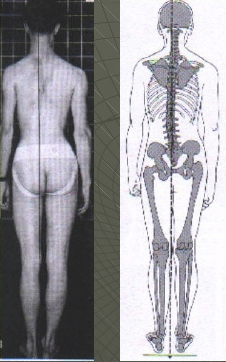

- Las características biomecánicas más relevantes son un aumento de la basculación anterior de la pelvis y una rotación medial de la rodilla.

Basculación lateral de la pelvis